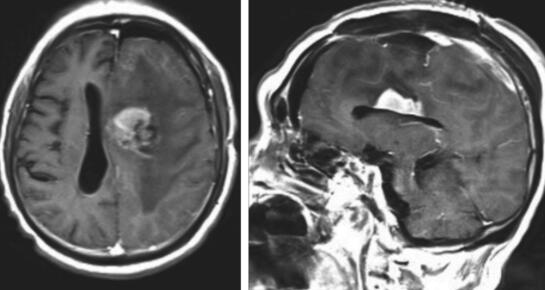

图2 患者2017年复查头颅MRI增强提示左额多发病灶,浅部病灶明显均匀强化;深部病灶不均匀强化,伴坏死

患者术后病理结果回报:(左额)不典型脑膜瘤(WHO Ⅱ级),免疫组化:EMA(+),VIM(+),stat6(-),PR(+),Ki-67(5%+),GFAP(-);(左额深部)恶性B细胞淋巴瘤,免疫组化:CD20(+),CD79a(+),Bcl2(+),Bcl6(部分+),CD3(-),Ki-67(70%+),PAX-5(+),CD10(-)。患者左额脑膜瘤和原发性中枢神经系统淋巴瘤(弥漫大B细胞型)诊断明确。患者术后一般状况可,遂先予甲泼尼龙激素治疗。患者术后复查头颅MRI提示淋巴瘤病灶较之前明显缩小(图4),继续予激素治疗,拟康复后转血液科行后续治疗。患者于术后第11天出现便血,停用激素并予支持对症处理后患者便血症状不能控制,反复消化道出血,于术后3周因“多脏器功能衰竭及消化道出血”宣告死亡。

图4 患者术后第二天复查头颅MRI提示左额深部病灶较术前明显缩小